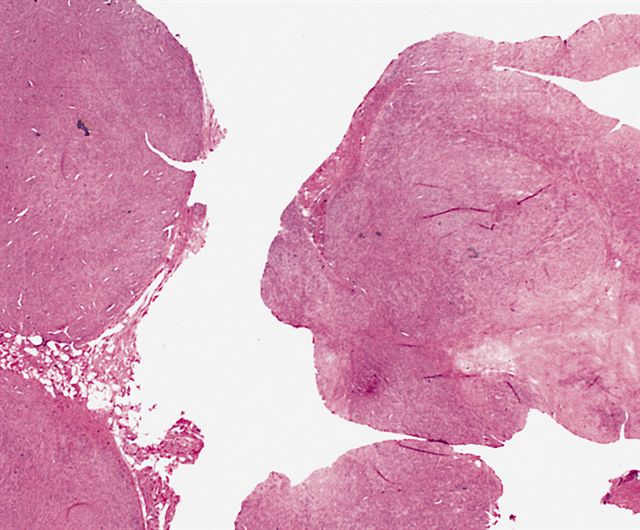

Microscopic (histologic) images

Contributed by Nasir Ud Din, M.B.B.S.

AFIP images

A 32 year old man has had painless swelling in the palm of his hand for 6 months. It was excised and the histology is shown in the above image. What is the most likely diagnosis?